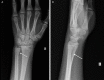

Isolated distal ulna epiphyseal plate injuries are very rare and are often associated with early epiphyseal plate arrest. A 13-year-old boy sustained an isolated minimally displaced Salter-Harris type II fracture of the left distal ulna following a fall from a bicycle. The fracture was reduced, and a long arm plaster cast was applied for four weeks. At the six-month follow-up, the patient presented with a painless, full range of movement of the left wrist, but on radiological examination, a mild shortening of the ulna was detected. We plan to regularly evaluate this patient until distal epiphyseal plate closure and surgically intervene if necessary. To our knowledge, this is the third Salter-Harris type II distal ulnar fracture ever reported, and the second treated nonoperatively. It was shown to be associated with a mild growth disturbance. Although Salter-Harris type II injuries are considered benign, surgeons should closely evaluate this rare type II isolated distal ulnar fracture and inform parents regarding possible future complications, which range from clinically insignificant cosmetic deformity to severe instability of the distal radioulnar joint, depending on the degree of shortening.